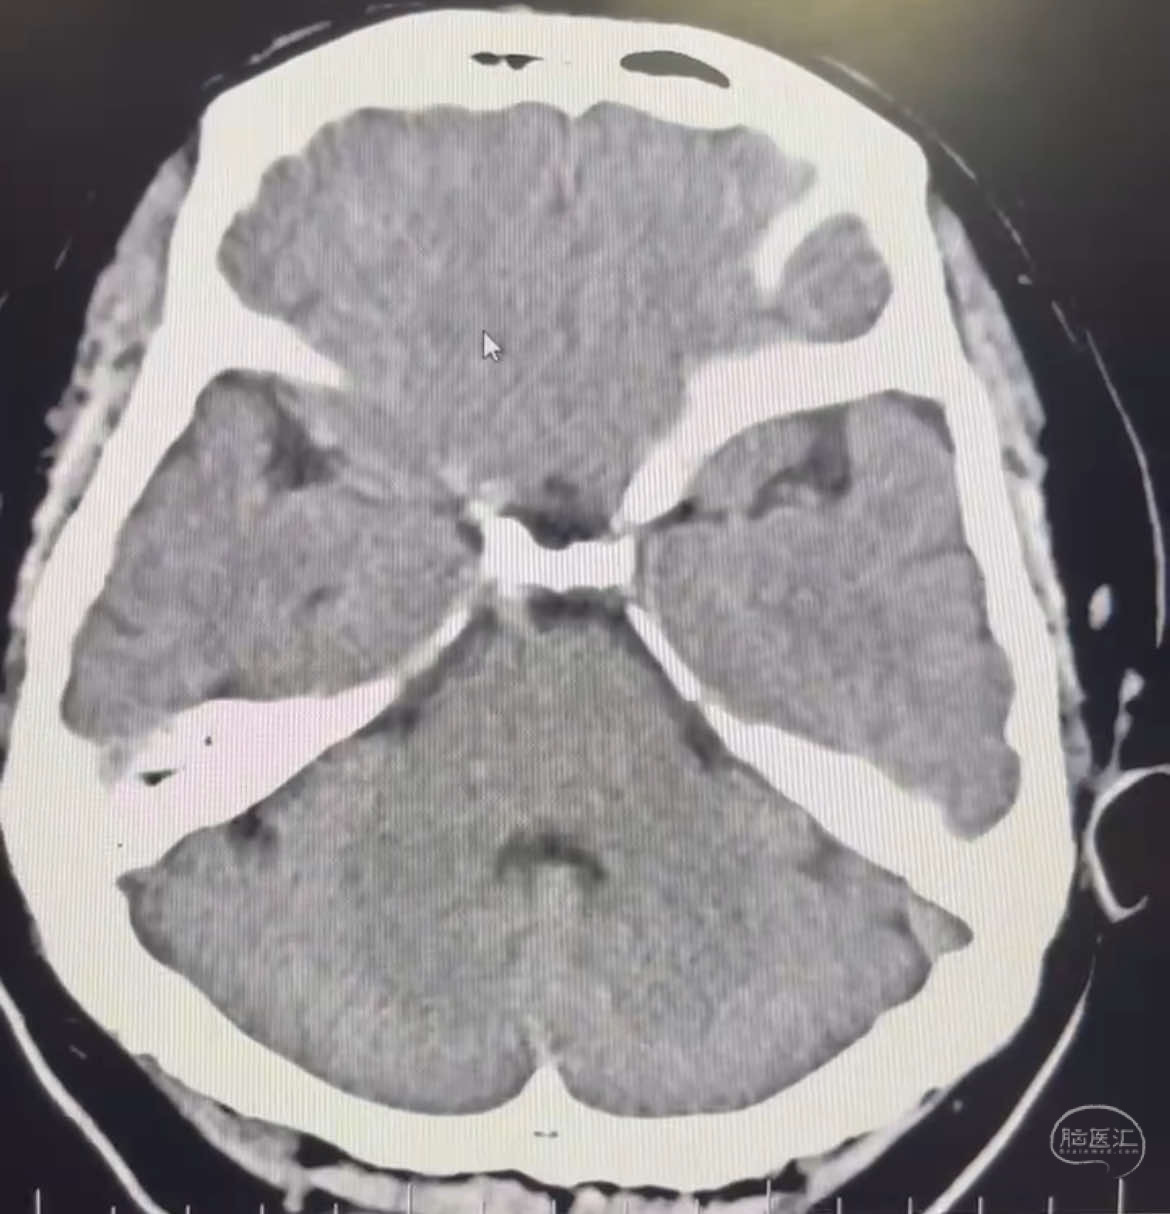

患者:LXS,M53Y,以“间断头晕头痛1周”为主诉入院,既往有高血压病及长期吸烟史。在当地医院行头颅CT未见异常,头颅MRA示右侧大脑中动脉M1段末端动脉瘤,左侧颈内动脉闭塞,交通动脉开放。

DSA示:左侧颈内动脉眼动脉段以远闭塞,后交通动脉开放,椎基底动脉通过后交通动脉代偿左侧大脑中动脉区域,右侧发出双侧大脑前动脉,右侧大脑中动脉M1末端宽颈动脉瘤,大小约4.3mmx4.6mm。